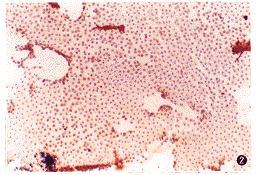

单核巨噬细胞是免疫系统的第一道防线,能独立鉴定抗原并提供信息传递,从而诱发免疫反应,在这些过程中释放一系列单核因子包括肿瘤坏死因子(TNFa)、白细胞介素一6(IL- VI)、白细胞介素-I(IL-I)等,亦称前炎性细胞因子。1.2 单核因子特点。单核因子具有来源的多样性、较高的生物活性以及与相应受体结合才能发挥生物活性等特点(杜念兴,1995)。但单核因子在动物生长代谢、内分泌及行为上具有较大的影响。

Clasing(1998)提出,在免疫应答中,单核因子的释放对受到免疫应激的动物代谢有重要的作用,这种假说是根据一系列试验得出的。当鸡处于各种炎症原中,降低了日采食量。日增重和饲料转化率,提高了机体的温度和血浆糖皮质激素,改变铁、铜、锌的重分配(Klsing,1987.1988),他们观察到体增重降低约有2/3源于采食量降低,其余归因于代谢改变。Klasing等(1981)从病诱导的巨噬细胞中分离上层无细胞的离心液,诱导相同的免疫反应,从上述试验结果可以看出是一种致免疫原成分,引起免疫反应和代谢改变。这种代谢改变总的表现为营养成分的重分配,即由支持生长和骨骼肌沉积转向支持免疫反应和抵抗疾病,这些变化包括:①提高了骨骼肌的动员,降低骨骼肌的沉积;②提高了基础代谢导致能量消耗;③日粮氨基酸(AA)作为糖异生的来源,降低了用作骨骼肌的沉积所需的AA;④肝脏合成大量急性期蛋白(ACP);⑤由于大量含金属离子的ACP合成,使铁、铜、锌发生重分配;⑥调节激素的分泌,如生长激素、胰岛素。胰高血糖素和糖皮质激素等的分泌;⑦能量的利用形式发生改变,许多组织动用大量体脂肪转化为糖以氧化供能。